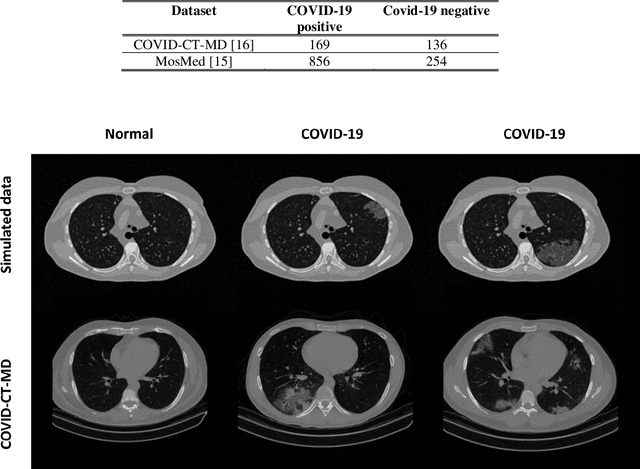

Abstract:Research studies of artificial intelligence models in medical imaging have been hampered by poor generalization. This problem has been especially concerning over the last year with numerous applications of deep learning for COVID-19 diagnosis. Virtual imaging trials (VITs) could provide a solution for objective evaluation of these models. In this work utilizing the VITs, we created the CVIT-COVID dataset including 180 virtually imaged computed tomography (CT) images from simulated COVID-19 and normal phantom models under different COVID-19 morphology and imaging properties. We evaluated the performance of an open-source, deep-learning model from the University of Waterloo trained with multi-institutional data and an in-house model trained with the open clinical dataset called MosMed. We further validated the model's performance against open clinical data of 305 CT images to understand virtual vs. real clinical data performance. The open-source model was published with nearly perfect performance on the original Waterloo dataset but showed a consistent performance drop in external testing on another clinical dataset (AUC=0.77) and our simulated CVIT-COVID dataset (AUC=0.55). The in-house model achieved an AUC of 0.87 while testing on the internal test set (MosMed test set). However, performance dropped to an AUC of 0.65 and 0.69 when evaluated on clinical and our simulated CVIT-COVID dataset. The VIT framework offered control over imaging conditions, allowing us to show there was no change in performance as CT exposure was changed from 28.5 to 57 mAs. The VIT framework also provided voxel-level ground truth, revealing that performance of in-house model was much higher at AUC=0.87 for diffuse COVID-19 infection size >2.65% lung volume versus AUC=0.52 for focal disease with <2.65% volume. The virtual imaging framework enabled these uniquely rigorous analyses of model performance.